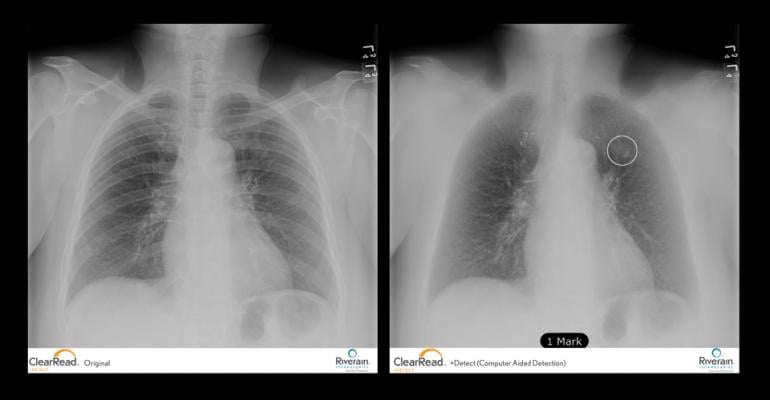

Riverain’s ClearRead bone suppression technology helps radiologists detect lung nodules and other serious medical conditions by transforming a traditional chest X-ray into a soft tissue image without the ribs and clavicle bones. These structures commonly obscure abnormalities. There are no additional tests or radiation exposure for patients, and no imaging machines or hardware for the hospital to buy or house to achieve the soft tissue image.

University of Chicago Medical Center, U-M Health System, Southern Ohio Medical Center, Riverside Medical Center in Kankakee, Ill., and the Hines VA Hospital in Hines, Ill., are some of the institutions that purchased ClearRead software. University of Chicago did so after serving as a research site and validating the strength of Riverain’s ClearRead Bone Suppression and computer-aided diagnosis (CAD) software, ClearRead +Detect, in improving the diagnostic potential of conventional X-ray images.

In addition to purchasing ClearRead Bone Suppression and ClearRead + Detect software, which marks suspected lung nodules on an X-ray image, U-M Health System physicians are moving forward with purchase of ClearRead +Confirm software based on a clinical evaluation of the software.